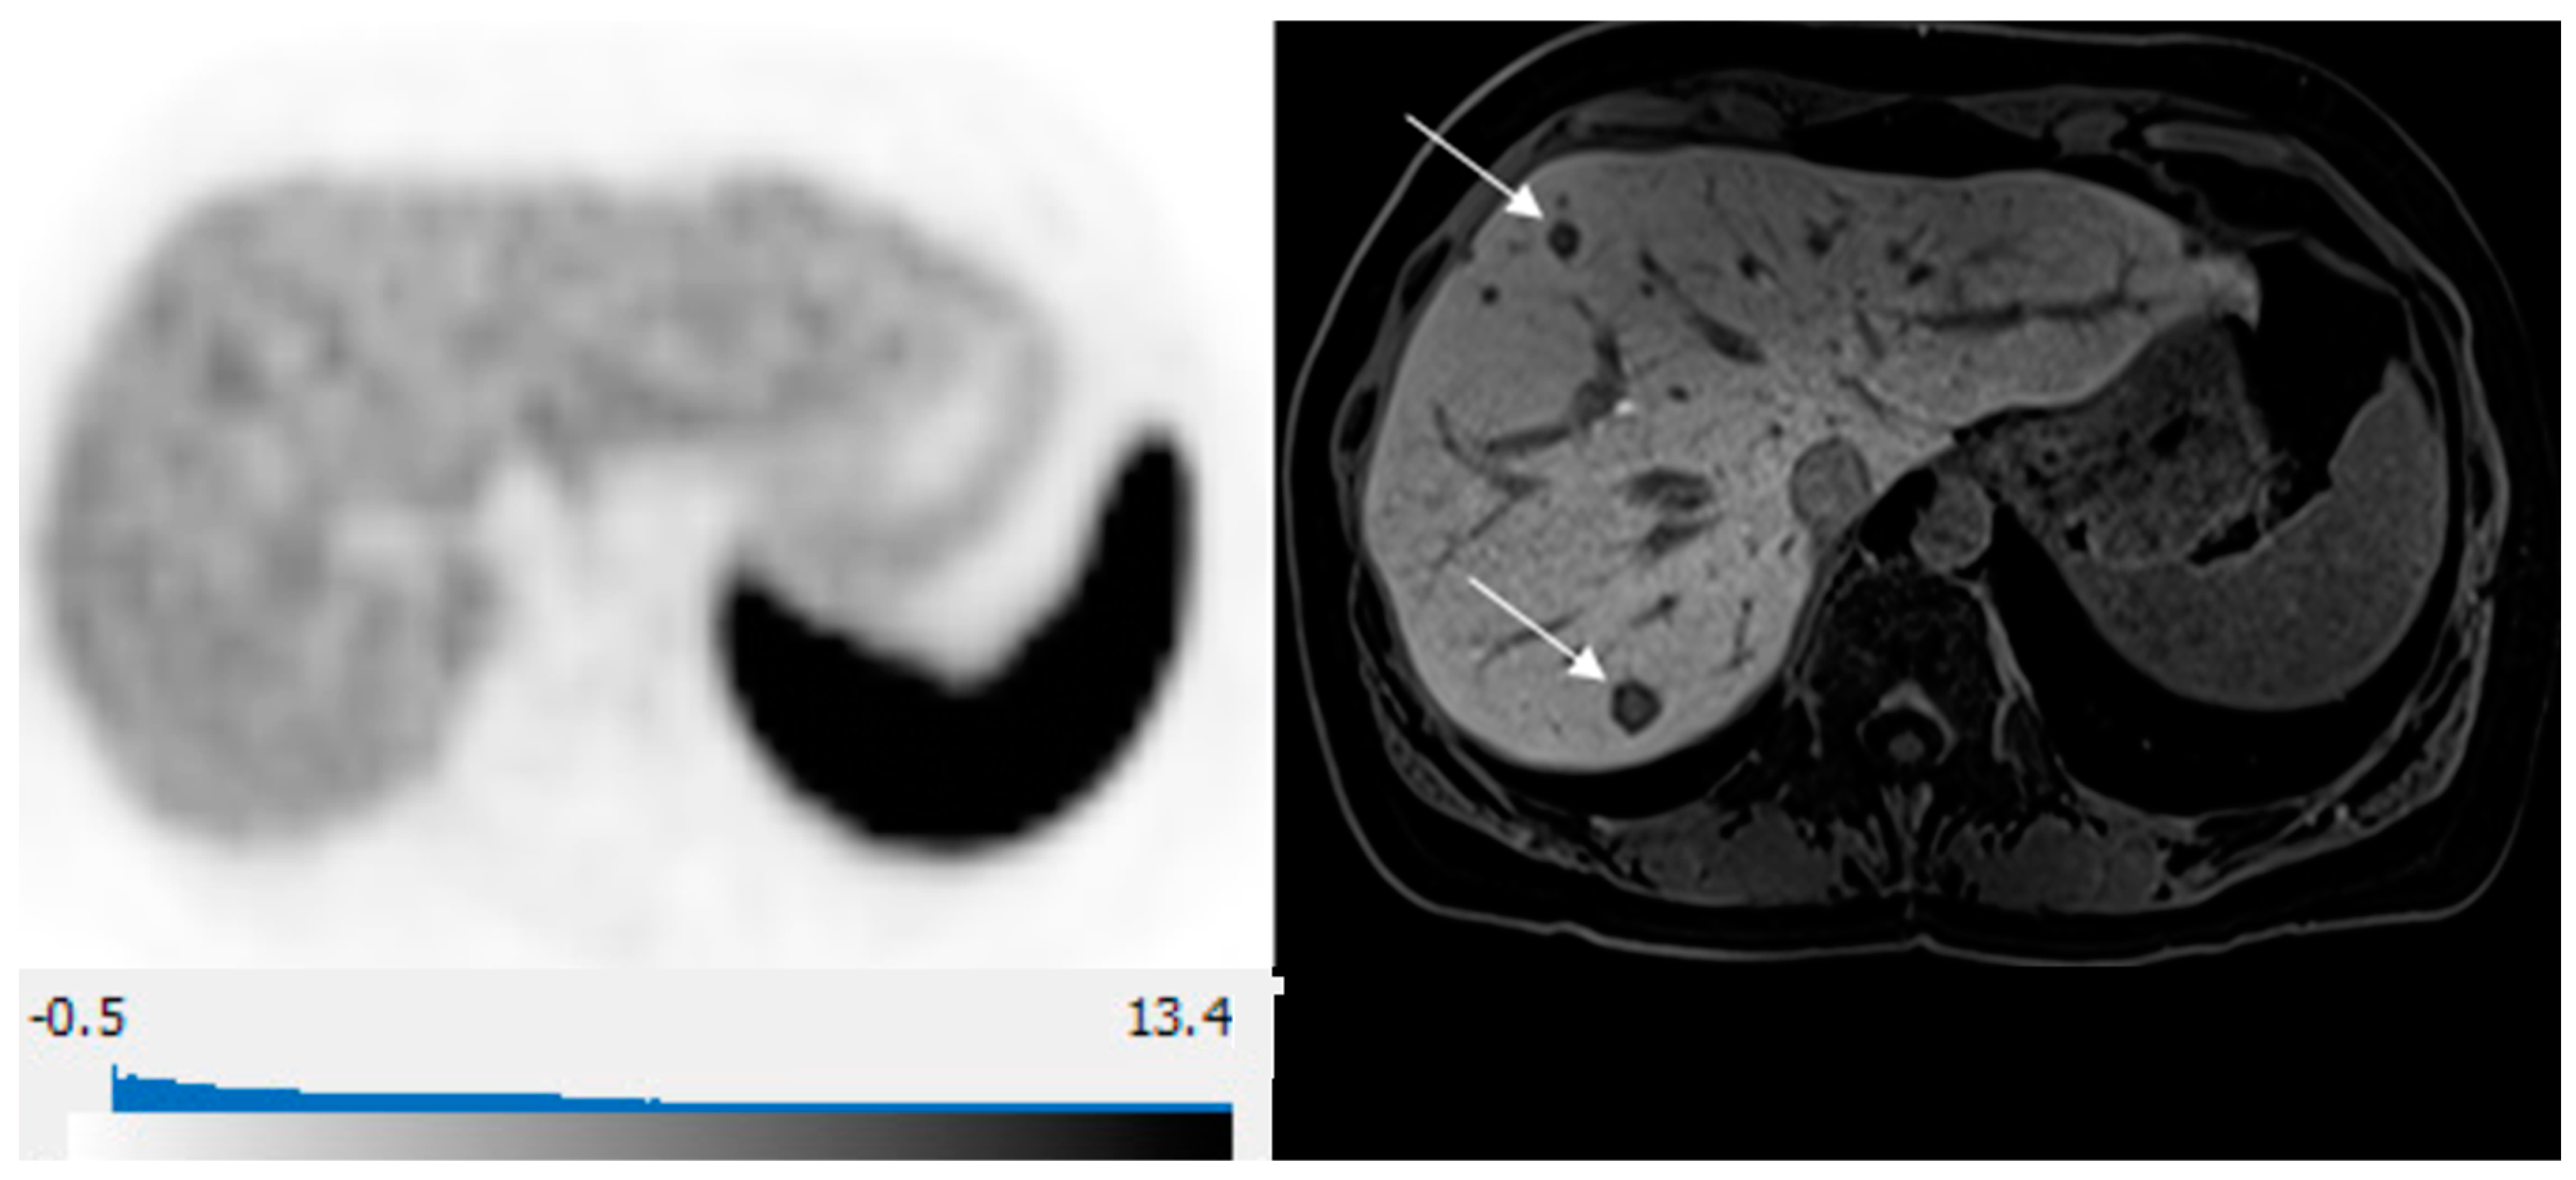

Figure 4.

65-year-old woman with well-differentiated G2 lung NET, 3 years following primary surgery. Axial 68Ga-DOTATATE PET at the liver dome (left) shows no focal radiotracer uptake corresponding to the 2 metastases depicted on corresponding axial hepatobiliary phase gadoxetic acid-enhanced T1 VIBE image (right; arrows) to suggest liver metastases over-expressing somatostatin receptors type 2.

The combination of diffusion-weighted imaging and hepatobiliary phase has been shown to yield the highest sensitivity and specificity in the detection of NLM, suggesting MR with hepatobiliary contrast agents is the modality of choice for assessment of disease extent in the liver in patients with NETs [43]. Our study confirms these findings with the highest detection of NLM on the hepatobiliary phase and DWI (Figure 4). A direct comparison of hepatobiliary-specific contrast-enhanced MR and conventional extracellular gadolinium-enhanced MRI has shown a significant impact of MR with hepatobiliary-specific contrast on the surgical management of patients with liver metastases [44]. To our knowledge, no prior studies compared hepatobiliary-specific contrast-enhanced MR and DT-PET in the detection of NLM. Our study demonstrates a similar diagnostic strength for both modalities in detecting NLM for tumors overexpressing somatostatin receptors but highlights the limitation of DT-PET when the somatostatin-receptor expression is low, and in these cases, pMR is crucial in accurately delineating disease extent. This is in line with prior reports of inverse correlation between tumor Ki67 index and SUVmax on 68Ga-DOTA-SSA PET [45]. Further studies comparing the utility of these modalities in NLM, especially for patients with intermediate or high Ki-67 index, are needed. We propose that future trials should assess the use of combined 68Ga-DOTATATE PET/gadoxetic acid MRI for NET patients with suspected liver metastases being considered for surgery or liver-directed therapies, such as focal tumor ablation or arterial chemoembolization. This approach will leverage the high detection rate of NLM, including the identification of subcentimeter liver deposits on pMR, along with whole-body staging for extrahepatic metastases with DT-PET.